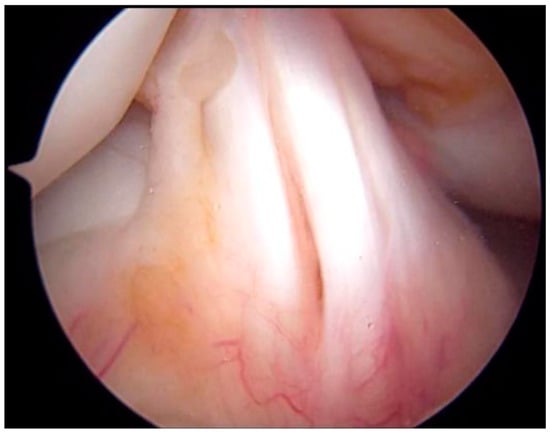

Type V Tibial Tubercle Avulsion Fracture with Suspected Complication of Anterior Cruciate Ligament Injury: A Case Report

2. Case Report